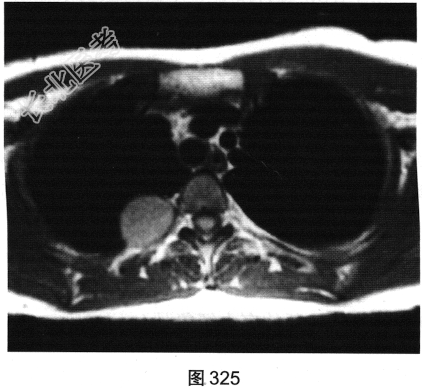

- [材料题] 患者女性,36岁,平素健康,无明显临床症状。单位体检拍摄胸部X线平片提示“右上肺阴影”。遂到大型医院进一步行胸部影像学检查,如图325~图327所示。

- 多项选择题2.关于该患者胸部MRI显示征象,正确的描述是( )

C、病灶位于右肺上叶后段胸膜下

D、病灶位于后纵隔脊椎旁区

E、在T,WI上呈高于肌肉的略高信号

F、在T2WI上呈高信号略欠均匀

G、冠状面示病灶可能来源于椎管内